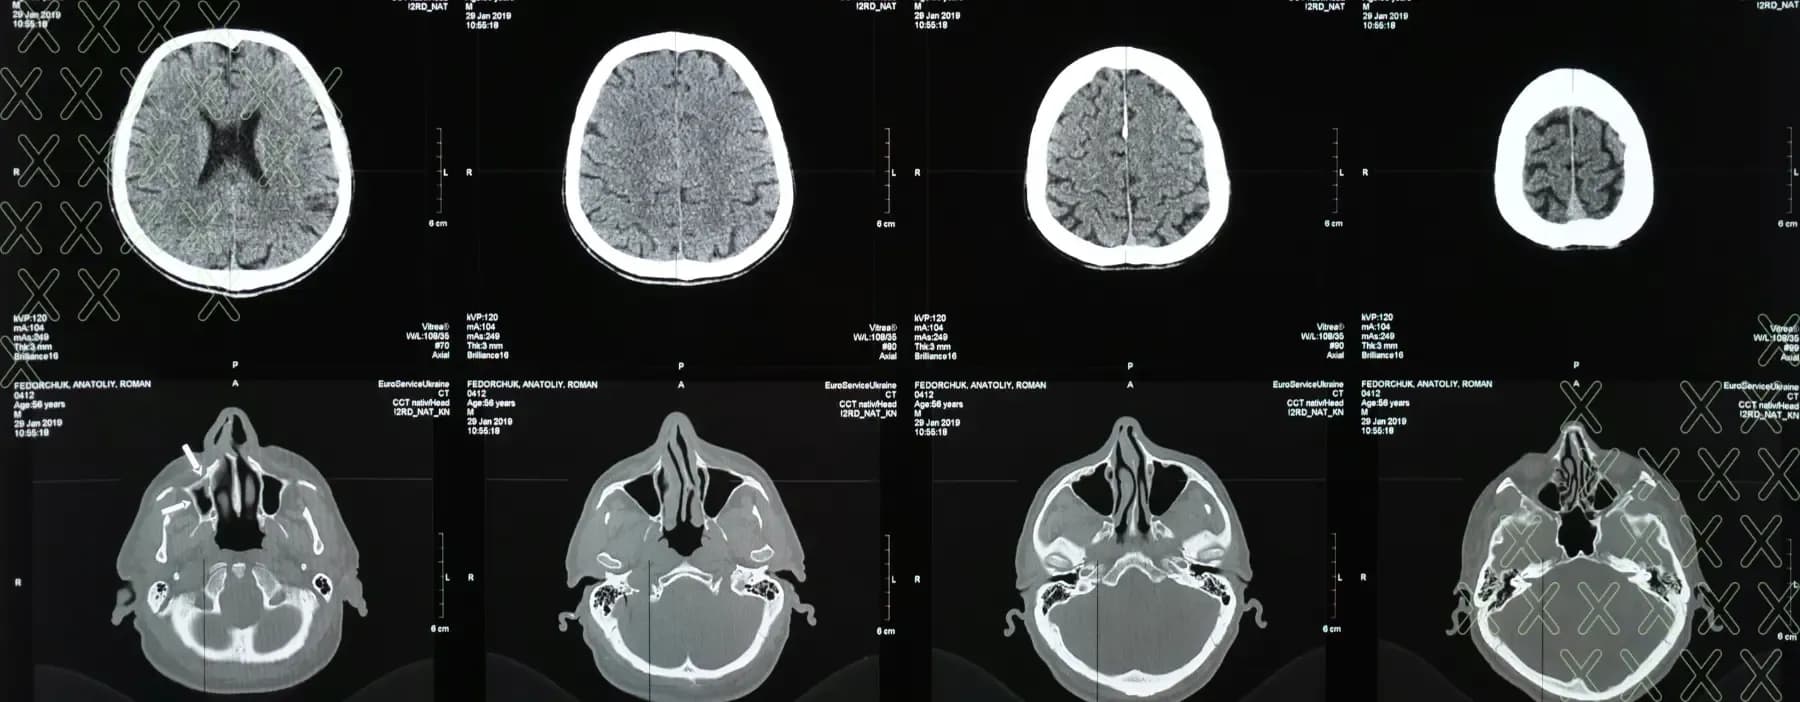

Researchers suggest that anatomical changes to the brain's medial temporal lobe (MTL) may be associated with the development of Alzheimer’s disease 12. Individuals with Alzheimer’s disease often exhibit abnormal accumulations of tau protein, forming neurofibrillary tangles within neurons, alongside excess beta-amyloid 42, leading to plaque formation. These neuronal changes are observed first in the MTL, implicating its role in auditory processing. Individuals with hearing loss also demonstrate MTL neuronal changes, suggesting an interplay between the two conditions.